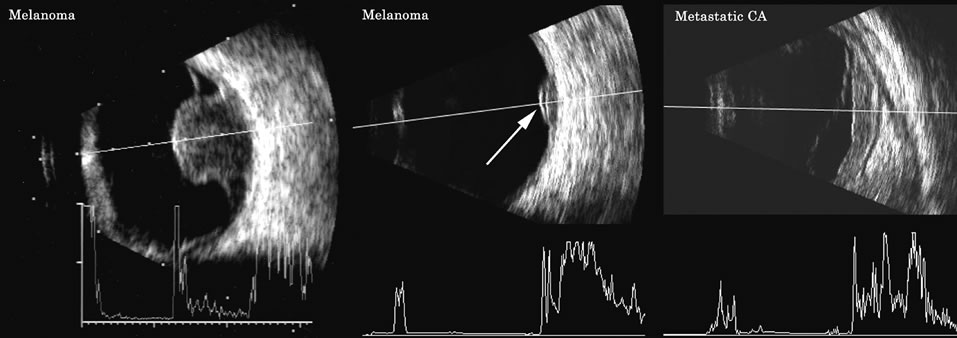

Malignant melanoma varies in its ultrasound presentation from a relatively homogeneous to heterogenous lesion on B-scan. The typical uveal melanoma absorbs sound so that the posterior section is relatively less echoic than the anterior aspect, producing a gradually decreasing amplitude, often to baseline on the A-scan (Fig. 21).

Fig. 21. An ocular tumor at the posterior pole showing the smooth convex border and solid internal reflectants typical of a melanoma.

Melanomas also have varying amounts of melanin, a highly acoustically reflective pigment. As noted, melanomas characteristically show high reflectivity anteriorly, with decreasing reflectance as the sound traverses the tissue. This produces the decreasing amplitude posteriorly in the tumor seen on A-scan and gray-scale B-scan. This effect often enhances the anterior scleral boundary. The posterior tumor border is thus measured as the first “rising” echo from the tumor decline, and it is most easily seen and accurately identified on B-scan.27

Metastatic carcinoma is more heterogeneous, producing a more uniform A-scan amplitude of roughly 50% to 80% of the “scleral” echo amplitude (see below) behind the tumor (Fig. 22). Hemangioma is a very highly reflective tumor with high amplitude all the way through the tumor of 80% to 100% of scleral echo amplitude (Fig. 23).

Fig. 22. Some hemangiomas and metastatic carcinomas may simulate a melanoma. They are differentiated on the basis of a very high amplitude internal echo complex for the hemangioma, a moderately low but sustained echo pattern for the metastasis, and an A-scan with decreasing reflectance as the tumor thickness is traversed. In the center scan of a melanoma, note the double anterior layer caused by edema fluid underlying the crest of the melanoma (arrow).